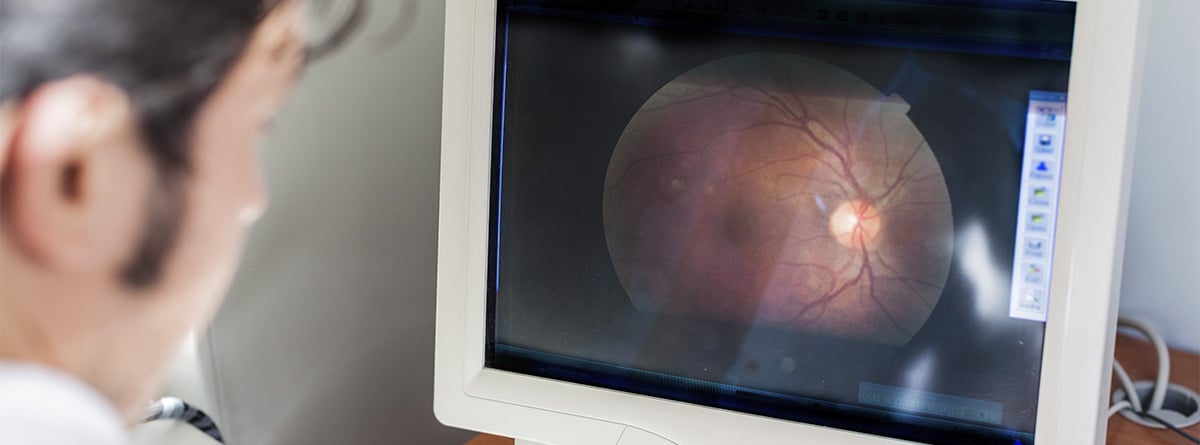

La oftalmoscopia o estudio del fondo del ojo es una técnica diagnóstica que consiste en visualizar el polo posterior del globo ocular, que incluye retina, disco óptico, coroides y vasos sanguíneos.

El estudio del fondo de ojo es una técnica relativamente sencilla que puede aportar mucha información al médico no sólo sobre enfermedades que pueden afectar únicamente al globo ocular como alteraciones de la retina, del nervio óptico o de los vasos sanguíneos; sino también sobre enfermedades sistémicas que puedan afectar y dañar al polo posterior produciendo pérdida visual importante o incluso ceguera como la diabetes mellitus o la hipertensión arterial entre otras. El estudio permite hacer diagnóstico y seguimiento de estas patologías.

- Consiste en visualizar la retina, disco óptico, coroides y vasos sanguíneos.